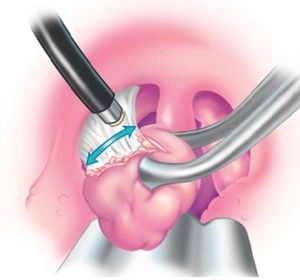

У разі, якщо систематичне лікування хронічного тонзиліту у дитини не дає позитивних результатів, мигдалини доводиться видаляти.